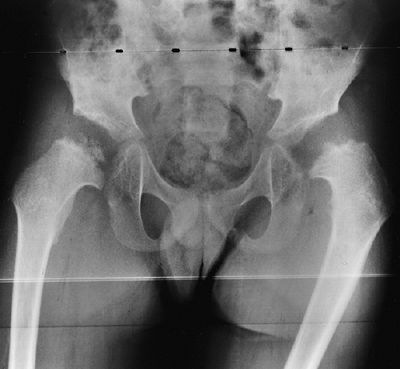

metaphyses of all long bones are flared in appearance. The diaphyses of

all long bones are thick, despite being short, owing to subperiosteal

bone apposition. Angulation at both the distal femoral and the proximal

tibial metaphyses contributes to abnormal knee alignment (Fig. 8.7).

The growth of the fibula is typically greater than that of the tibia,

and this also contributes to the varus in some cases. The shape of the

distal femoral physis is an exaggeration of the normal inverted “V” in

![]() |

Figure 8.7

Radiograph of the lower extremities in a six-year-old with achondroplasia. The distal femoral physes have a pronounced inverted-“V” shape, and the knee is in varus. The acetabular roofs are horizontal. |